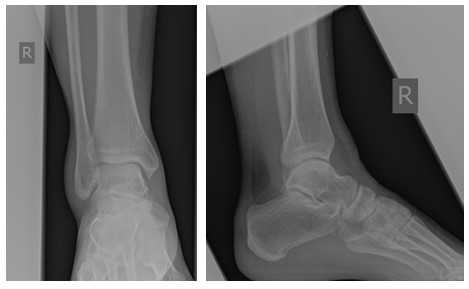

История неоднократных травм голеностопного сустава на протяжении более 10 лет, в среднем 2-3 раза в год подворачивает ногу, после чего наблюдается в травмпункте в связи с болями в голеностопном суставе. Обратилась к нам в клинику из-за того что после последнего эпизода подворачивания стопы боль держалась дольше обычного, и была более интенсивной. На стандартных рентгенограммах - без патологии.

На этом этапе пациентка лечилась по стандартному сценарию «растяжение голеностопа». Носила ортез, мазала голеностоп вольтареном и лиотоном, разгружала его при помощи трости. Но в связи с длительно сохраняющимся болевым синдромом было выполнено МРТ, при котором диагностирован застарелый разрыв передней таранно-малоберцовой связки, пяточно-малоберцовой связки правого голеностопного сустава, контузионное повреждение латеральных отделов таранной кости.